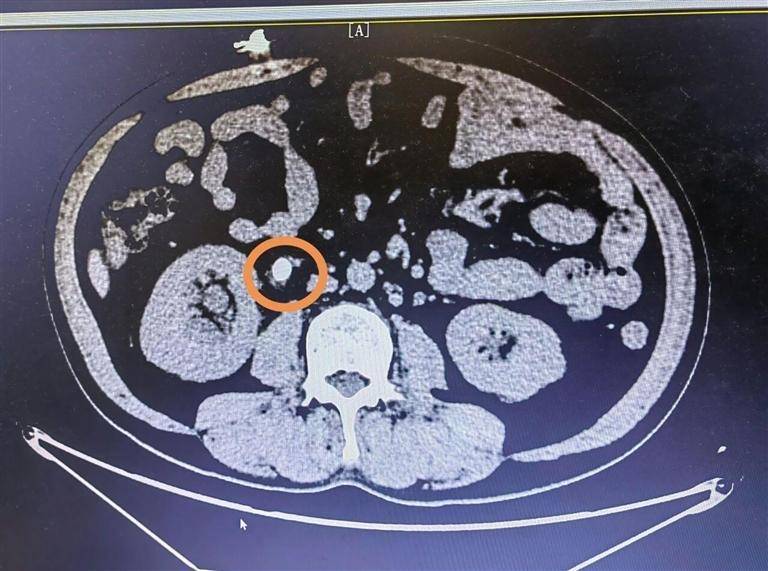

一周前,陈先生突发右侧腰腹部剧痛,疼痛还放射至会阴部,被诊断为“右侧输尿管结石伴肾积水”。虽经初步治疗缓解了症状,但结石未被清除,病根仍在。随后他接受体外碎石治疗,可效果不佳,结石始终无法排出。不久后,陈先生出现寒战、高热症状,体温飙升至39度,病情急剧恶化,被紧急送往秦皇医院。

“患者入院时情况十分危急,这已不是普通的结石疼痛,而是感染引发的急症!”接诊的秦皇医院泌尿外科林西斌主任表示,经检查,陈先生被确诊为“右侧输尿管结石伴有积水和感染”。由于结石阻塞输尿管,尿液滞留导致细菌在肾盂内大量繁殖,毒素随时可能进入血液,引发脓毒血症或感染性休克,“必须立刻手术,否则会严重危及生命。”而如何在清除结石的同时控制感染扩散,成为手术团队面临的关键挑战。